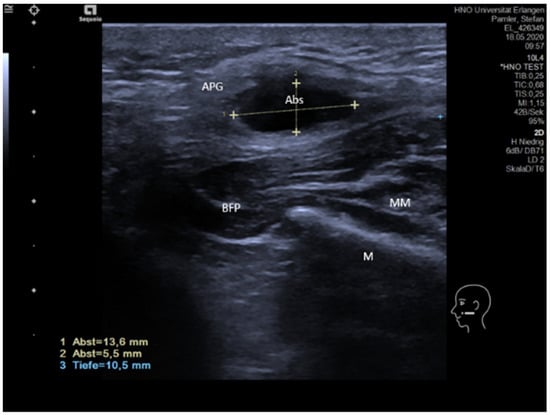

3.4.4. IgG4-Associated Involvement of Salivary Glands